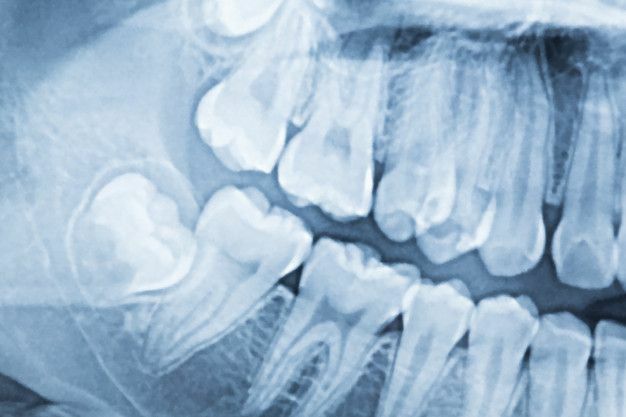

• la radiografia dental

la radiografia dental

El Dr. Otto Walkhoff (Alemania) haría la primera radiografía dental, con una exposición de 23 minutos. El Dr. Edmund Kells tomo la primera radiografía intraoral, siendo el primer dentista que utilizaba esta técnica en procedimientos odontológicos